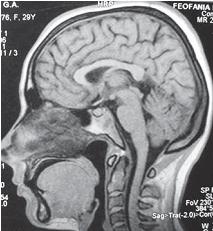

МРТ № 46

Возьмём за вариант нормы данный снимок МРТ № 46, на котором наблюдается нормально выраженный лордоз, высота межпозвонковых дисков, ширина позвоночного канала. Самое главное — отсутствие стеноза (сужения).

Спинной мозг: контуры ровные, чёткие, структура гомогенная (греч. homogees — однородный), расположен почти в центре позвоночного канала и имеет нормальную толщину. Участков его патологического расширения или сужения не наблюдается. Ликворные пути свободны, проходимы.